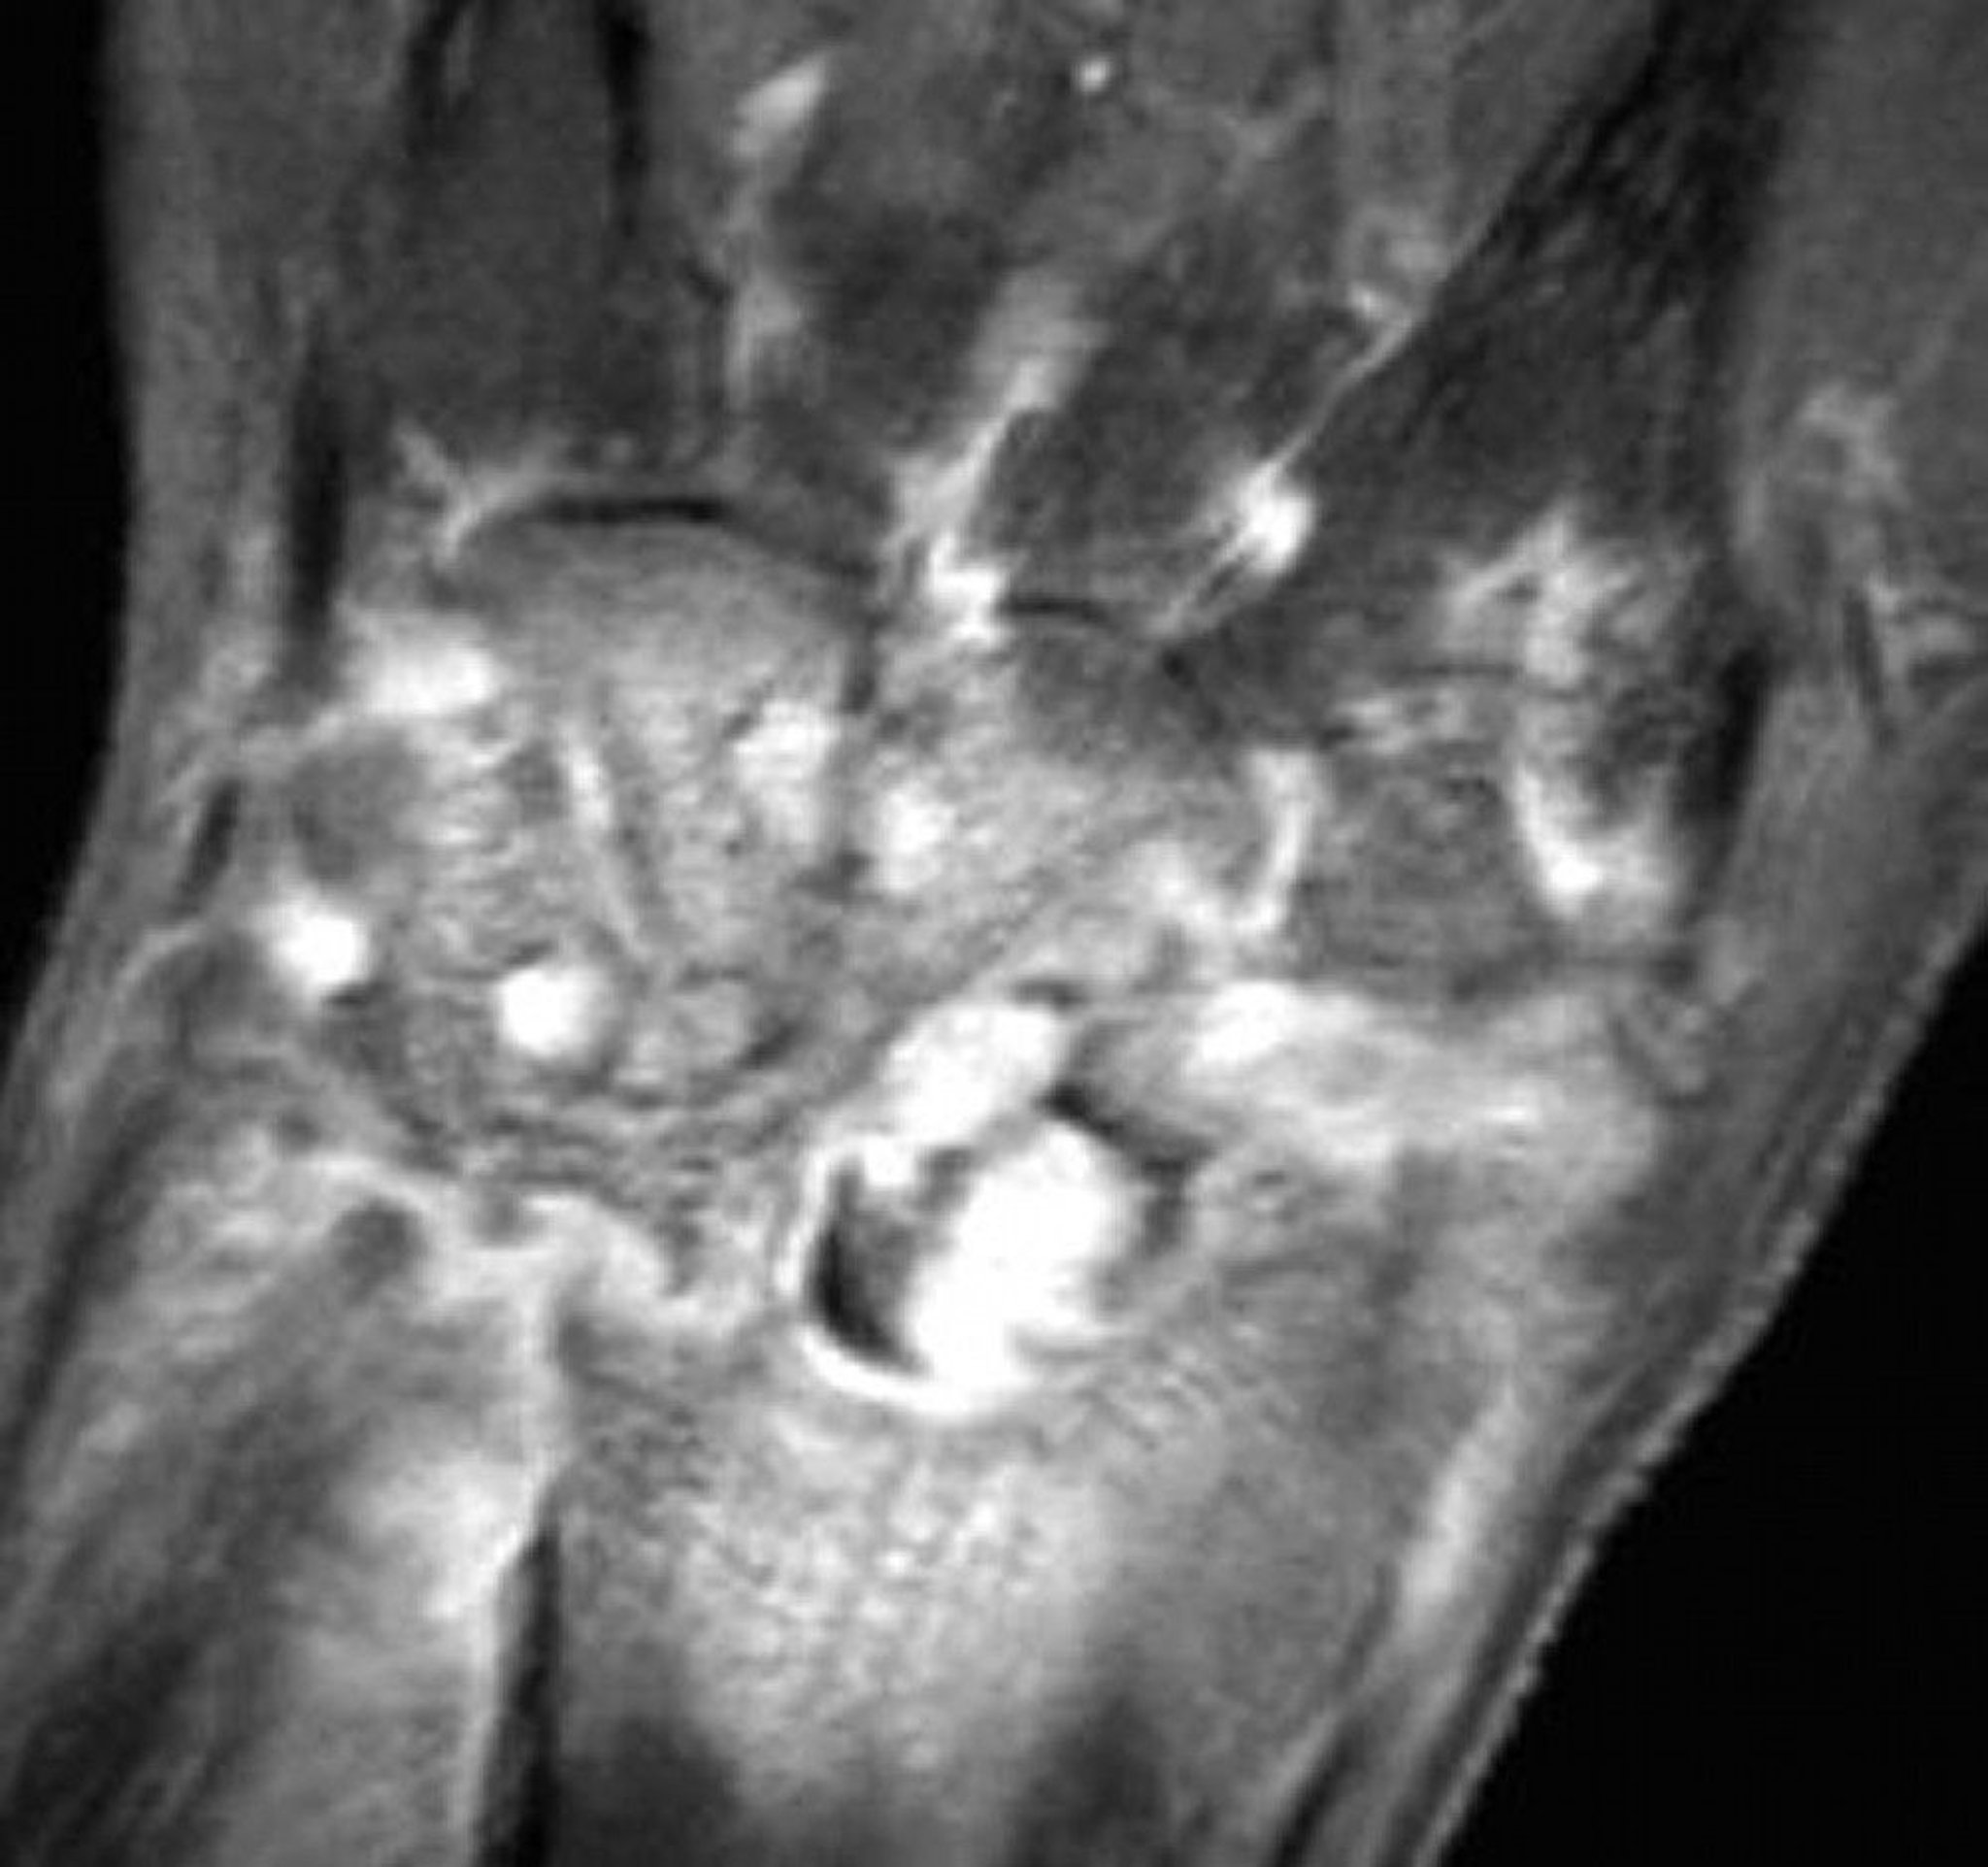

MRI of Gonococcal Arthritis in the Wrist

This T1-weighted coronal fat-suppressed MRI with gadolinium of a wrist with gonococcal septic arthritis shows diffuse synovial enhancement and erosions.